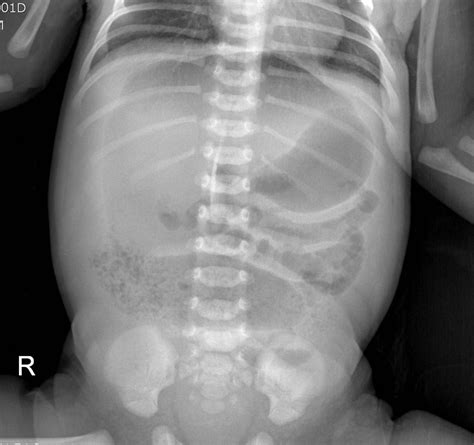

• Imaging Tests: In some cases, imaging tests such as X-rays or ultrasounds may be ordered to visualize the intestines and identify any blockages or abnormalities.